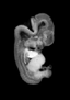

Carnegie Stage 20 (50 post-ovulatory days)

Most embryos at stage 20 are approximately 50-51 postovulatory days old and measure 21-23 mm in length. Distinguishing criteria for this stage include upper limbs slightly bent at the elbows, short stubby fingers, hands curving over the cardiac region but still far apart from each other, and a fringe-like vascular plexus that marks growth centers laterally in the superficial tissues of the head.

Although some of the photographs below show abnormal embryos, the animations and MRI slice images all depict normal embryos. Abnormal embryos are noted in the titles of the large photos when they are opened.

Photographs